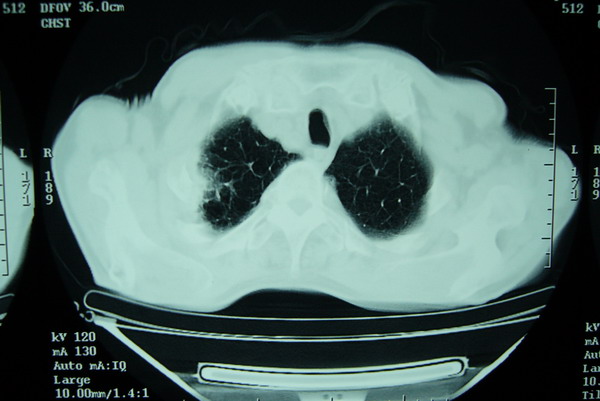

标题: CT15579:男 86岁 咳嗽 咳少量白痰 发热2天 吸烟史60年 [打印本页]

标题: CT15579:男 86岁 咳嗽 咳少量白痰 发热2天 吸烟史60年

右上周围型肺癌,慢支,肺气肿。

分叶及少量边缘性钙化,老年人,周围性肺癌首先考虑。